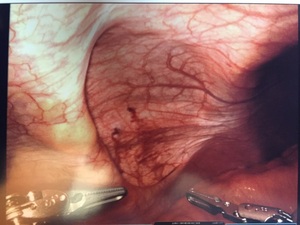

The intercostal defect was measured and a 7.6 x 13 cm. oval shaped Sepramesh (Bard Davol Inc. Providence RI) was brought onto the surgical field. Primary closure of the defect was not performed. The mesh was anchored in place at the antero-medial and posterolateral ends utilizing 2-0 Vicryl (Ethicon Inc, Somerville, NJ). The mesh was then affixed circumferentially utilizing a 2-0 V-lock (Medtronic, Fridley, MN) suture in a running fashion with a 2cm. overlap of normal tissue. The ribs were not incorporated in the suture (Figure 4).